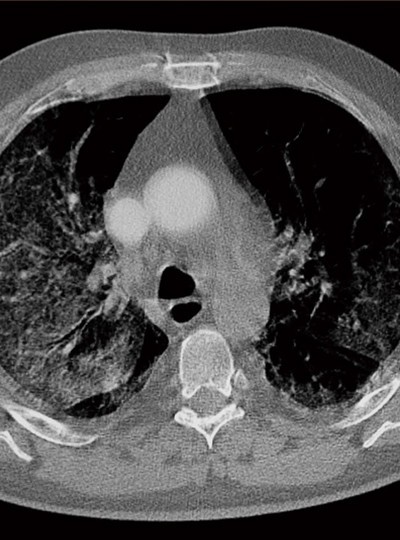

ITALY Catania, Sicilia. April 9 2020.

CT scan of the lungs of a patient with Covid 19 virus.

위 사진은 2020년 4월 9일, 코로나19에 감염된 사람의 폐를 CT 촬영한 것이다.

바이러스가 폐 혈관을 따라 걷잡을 수 없이 퍼진 적나라한 이미지는 바이러스에 대한 공포와 경각심을 불러일으킨다.